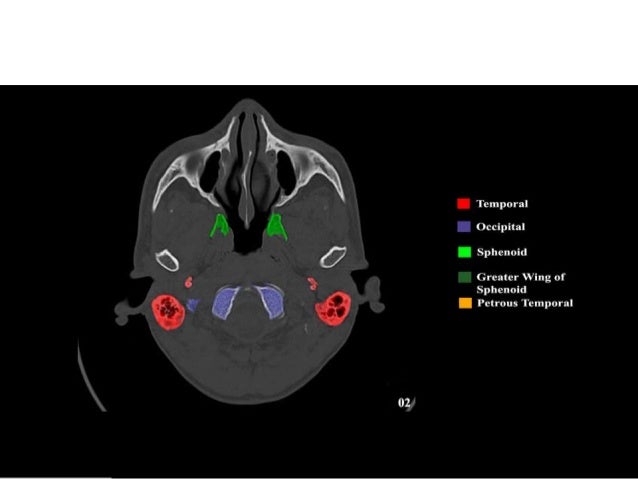

The sphenoid bone is a single, complex bone of the central skull ().

Skull base anatomy and cranial nerves explained in a simple way to remember it and use it in your daily practice as a radiation. It shows the thin cortical margins of skull base neurovascular foramina. Inferior view of base of the skull. The skull has inner and outer tables of cortical bone with central cancellous bone called 'diploe'.